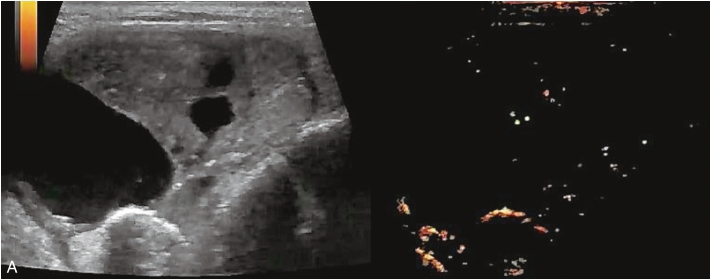

女性,65岁,发现“右侧颈部肿块2年余”就诊,其他无特殊。

甲状腺腺瘤伴囊性变常规超声图像,见图1-3-22。

图1-3-22 甲状腺腺瘤伴囊性变常规超声示意图

A.灰阶图像示甲状腺右叶内可见以囊为主的混合回声,边缘光滑,纵横比<1,实性部分呈等回声,回声均匀;B.CDFI血流成像示结节内部及边缘可见丰富血流信号

甲状腺腺瘤伴囊性变超声造影图像,见图1-3-23、ER1-3-11。

甲状腺腺瘤伴囊性变超声造影表现为病变内实性部分与周围正常甲状腺组织同步或稍早于周围甲状腺组织,呈弥漫性均匀性等增强或稍高增强,与周围正常甲状腺组织同步消退。病灶囊性部分呈无增强。病灶边缘可见环状高增强。

实性部分超声造影多表现为呈均匀或不均匀等增强,结节边缘无环状高增强。

实性部分超声造影达峰时多表现为不均匀低增强。

图1-3-23 甲状腺腺瘤伴囊性变超声造影图

A.增强早期;B.达峰时;C.增强晚期

ER1-3-11 甲状腺腺瘤伴囊性变超声造影视频

视频注解:在造影剂注射后10s病灶实质部分与甲状腺实质同步增强、同步廓清呈等增强,囊性部分呈无增强,结节周边可见环状高增强